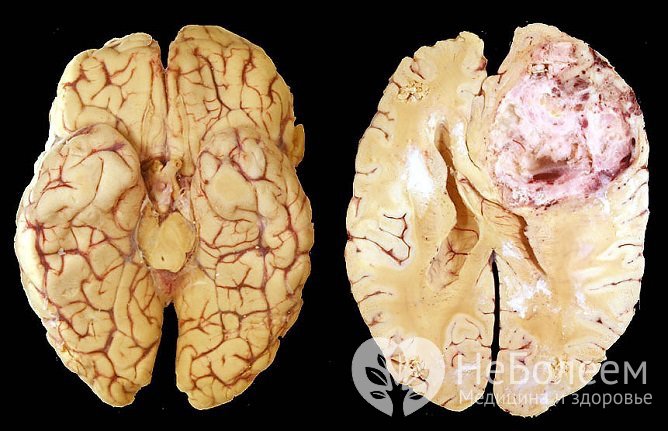

Мультиформная глиобластома, внешний видПо степени злокачественности выделяются:

Глиомы имеют веретенообразную или округлую форму, от 2-4 мм до 10 см в диаметре. Они характеризуются медленным ростом и отсутствием метастазирования, однако при этом способны к выраженному инфильтративному росту, то есть к прорастанию в окружающие ткани. Нередко найти границу между здоровыми тканями и глиомой не удается даже при помощи микроскопа. Еще одной особенностью является развитие дегенеративных процессов в окружающих тканях. В итоге наблюдается несоответствие между выраженностью неврологической симптоматики и размерами глиомы.

Полное хирургическое удаление глиомы головного мозга возможно только при условии абсолютной доброкачественности опухоли (I степень злокачественности). Во всех других случаях глиомы быстро прорастают в окружающие ткани, что усложняет задачу. Использование в ходе оперативного вмешательства МРТ-сканирования, интраоперационного картирования головного мозга, микрохирургических техник позволяет провести резекцию глиомы в пределах здоровых тканей максимально полно, что значительно сокращает риск рецидива заболевания.